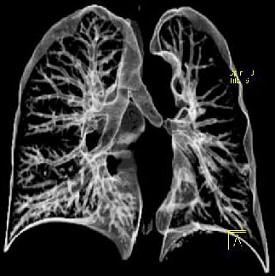

男,45岁,外伤后行CT检查如图,最可能的诊断为 ( )A、肺大疱B、支气管囊肿并感染C、左主支气管断裂D、畸胎瘤E、支气管肺炎

问题 男,45岁,外伤后行CT检查如图,最可能的诊断为 ( )

选项 A、肺大疱 B、支气管囊肿并感染 C、左主支气管断裂 D、畸胎瘤 E、支气管肺炎

答案 C